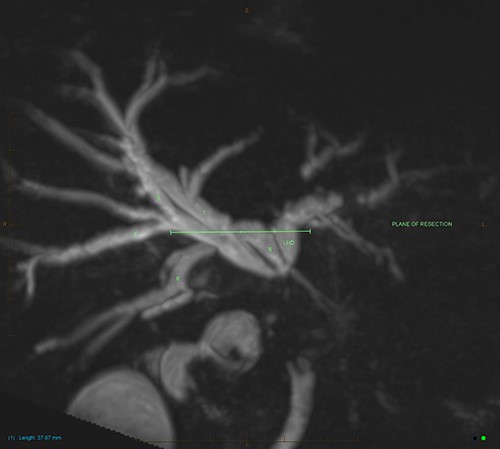

MIP reconstruction of 3D MRCP reveals abrupt segmental stricture of the common hepatic duct with marked intrahepatic biliary dilation. Trifurcation of the biliary confluence into the left hepatic duct, aberrant segment 6 duct and the right hepatic duct. The right hepatic duct is formed by the union of right anterior (segment 5,8) duct and segment 7 duct while the segment 6 duct is joining separately at the confluence. The approximate plane of surgical resection is indicated.

An endoscopic retrograde cholangiopancreatography procedure (ERCP) confirmed a likely malignant biliary stricture in the extrahepatic duct and a plastic biliary stent was placed for biliary decompression. An FDG-PET scan revealed intense FDG uptake in the extrahepatic bile duct, with mild FDG uptake in two lymph nodes surrounding the gallbladder neck with no distant metastasis. Multidisciplinary consensus was obtained to proceed to surgery in the setting of likely EHC.

The patient underwent an open pancreaticoduodenectomy and cholecystectomy. Surgical resection was extended proximally to include the biliary confluence and biliary transection was performed to reveal four separate bile duct openings consisting of the right anterior and posterior sectoral ducts, a separate segment 6 duct and the left hepatic duct (Fig. 4).